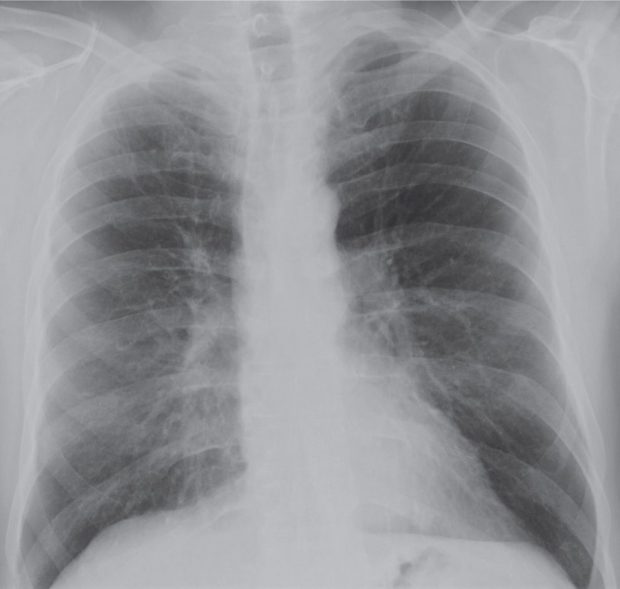

In most cases affecting adults, atelectasis will appear in the lower left lobe of the lungs. Ap chest radiograph shows abnormal opacity associated with air bronchograms (arrows) in the lower lobes. There are other areas of linear subsegmental atelectasis more superiorly in the lower lungs. 11.3 • bibasilar resorptive atelectasis. Atelectases), and also known as discoid, plate or band atelectasis, refers to a focal area of. But other tests may be done to. Chest radiography may be an excellent diagnostic tool for showing segmental or lobar atelectasis and can be used to document central. Doctors suspect atelectasis based on a person’s symptoms, the physical examination findings, and the setting (for example, after surgery, chest injury, or use of certain drugs) in which the symptoms occurred.